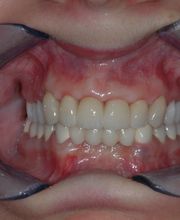

Das Bodensee Implantat Zentrum (ZIP) ist Ihre führende Praxis für Zahnheilkunde in der Region. Wir sind spezialisiert auf hochwertige Implantologie, einschliesslich des All-on-4® Konzepts, für das wir als Excellence Center Gold-zertifiziert sind. Unser Leistungsspektrum umfasst Komplettsanierungen, Kronen, Brücken sowie ästhetische Behandlungen. Mit über 30 Jahren Erfahrung bieten wir auch Angstpatienten eine einfühlsame Betreuung und Behandlungen unter Narkose für ein strahlendes Lächeln.